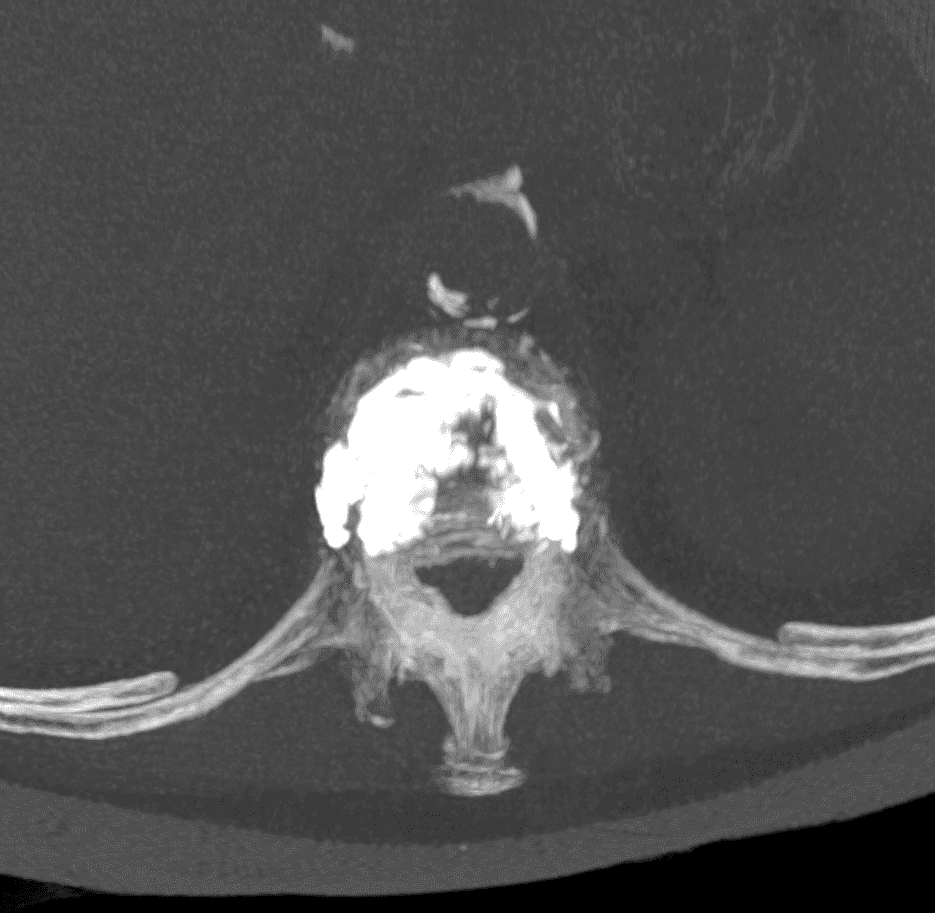

Insertion et déploiement de l’implant

L’implant SPINEJACK est introduit dans le corps vertébral. Une fois en place, il est progressivement déployé pour redresser la vertèbre et restaurer sa hauteur, améliorant ainsi la posture et réduisant la douleur.

Injection du ciment

Pour assurer la stabilité de l’ensemble, du ciment osseux est injecté de manière contrôlée autour de l’implant, garantissant ainsi la consolidation et la pérennité du résultat.